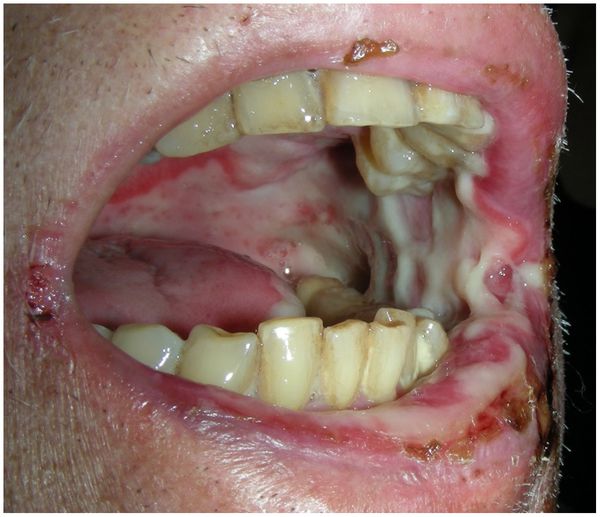

Перерыв в лечении или изменение режима. Если из-за лучевой или химиотерапии развивается тяжёлая степень мукозита, врачу приходится уменьшить дозу препаратов или радиации или отложить курс, что снижает эффективность лечения.

![Тяжёлая степень мукозита [24]](/pimg3/mukozit-prichini-simptomi-7957.jpeg)

Вторичная инфекция. Через поражённую слизистую оболочку полости рта в организм, ослабленный после лучевой или химиотерапии, могут попасть патогенные микроорганизмы. В этом случае на фоне мукозита развивается вторичная бактериальная, грибковая или вирусная инфекция. Проведённые исследования показывают, что у 29,1 % пациентов, проходящих лечение от рака, был выявлен простой герпес, который усугублял язвенный мукозит полости рта [3] [12] .

Сепсис. Если вторичную инфекцию не лечить, патогенные микроорганизмы могут массово попасть в кровоток и распространиться по всему организму. Такая тяжёлая системная инфекция называется сепсисом. Он может стать причиной смерти [17] [18] .